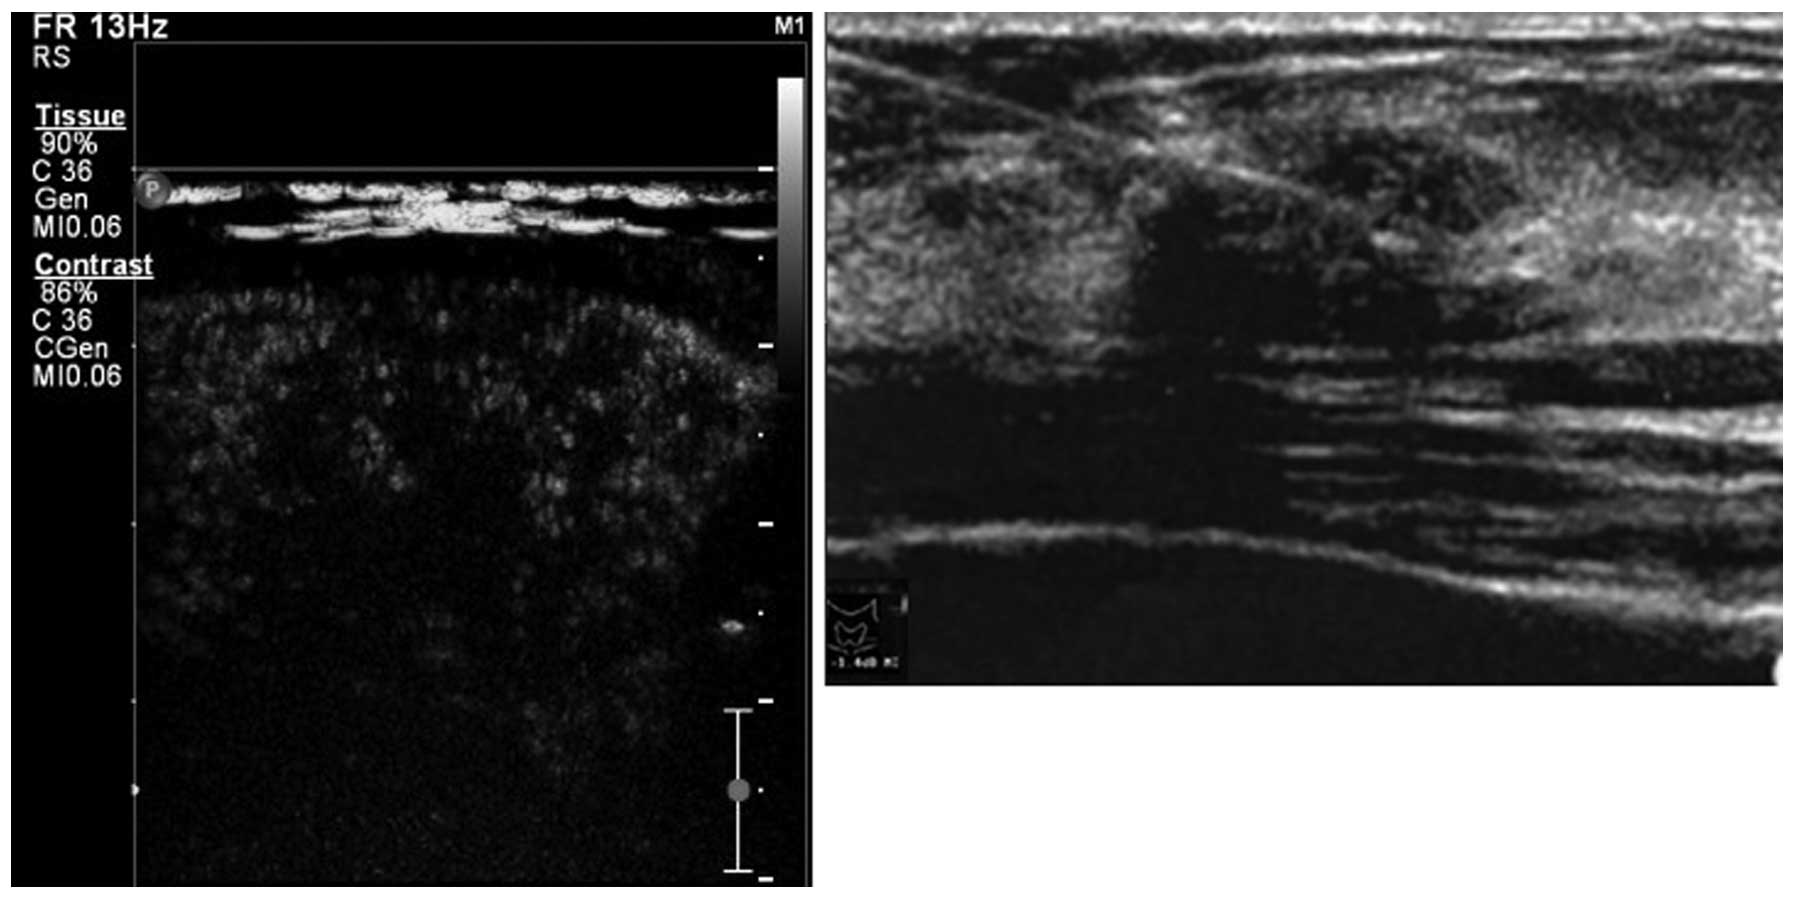

There were three types of manifestation, including irregular weak concentric ring enhancement (Fig. 1), no or weak enhancement (Fig. 2) and uneven enhancement (Fig. 3) in the CEUS images of the 51 nodules in 48 patients. All nodules provided adequate specimens and the satisfaction rate of tissue drawing was 100%. Of the 51 nodules, 44 (86.3%), five (9.8%) and two (3.9%) nodules were pathologically diagnosed as PTC, nodular goiter and focal Hashimoto’s disease, respectively. From the 44 nodules diagnosed as PTC, 43 (97.7%) and 34 (77.3%) nodules were detected by CEUS and conventional ultrasound, respectively, with a significant difference between the two methods (P=0.022). Eleven (25%) nodules were independently detected by CEUS and 31 (70.5%) nodules were detected by CEUS and conventional ultrasound. Only one nodule was not detected (2.3%).

Figure 2

Weak enhancement by CEUS (pathologically diagnosed as PTC). CEUS, contrast-enhanced ultrasonography; PTC, papillary thyroid carcinoma.